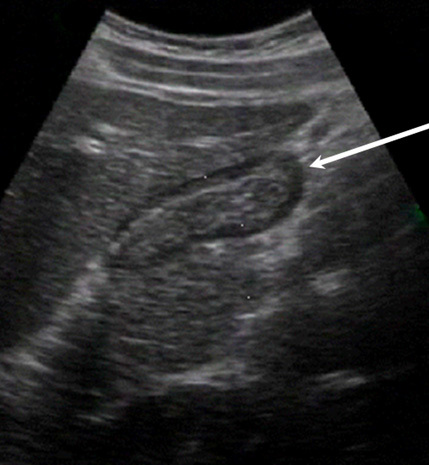

Gallbladder Duodenum Gas Image

Arrow: Duodenum Gas